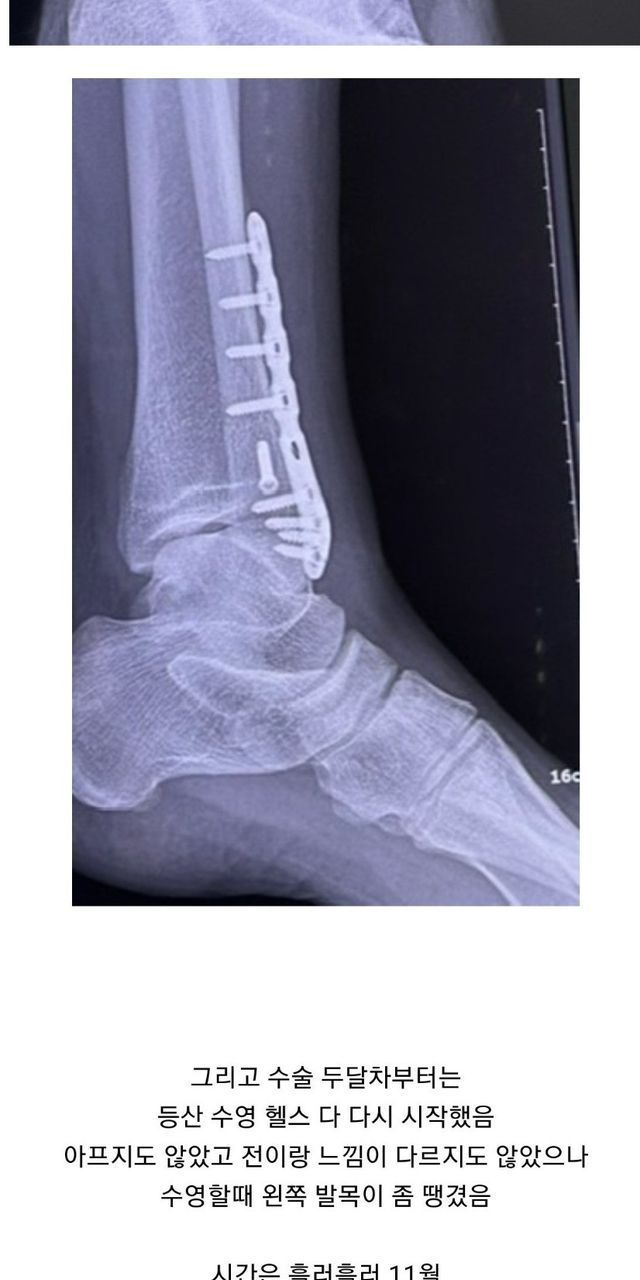

원래는 1년뒤 철심빼기로 했는데 백수되고 한가해서 이참에 하자고 수술날짜 땡겨서 1월초로 수술 잡힘

근데 어차피 시간 남아돌아서 지금하는게 나을거같길래 또 땡겨서 12월에 수술

다음날 걸어다니는거 보고 의사 또 화들짝 바로 퇴원함

그리고 2024년 1월달에 한라산 등산할거라 실밥좀 풀어달라했는데 거절

몸 인증도 했는데 자기 운동 좋아해서 다양하게 한다고 함